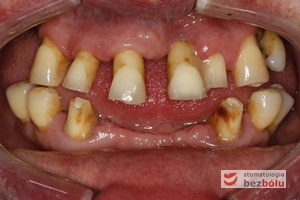

Stan wyjściowy - patologiczne wychylenie zębów górnych, liczne braki zębowe w szczęce i żuchwie, nieproporcjonalnie małe zęby do podstaw kostnych

Stan wyjściowy – patologiczne wychylenie zębów górnych, liczne braki zębowe w szczęce i żuchwie, nieproporcjonalnie małe zęby do podstaw kostnych

Braki zębowe w strefach bocznych szczęki i żuchwy - widoczne starcie patologiczne na skutek przeciążeń okluzyjnych w odcinku przednim

Braki zębowe w strefach bocznych szczęki i żuchwy – widoczne starcie patologiczne na skutek przeciążeń okluzyjnych w odcinku przednim